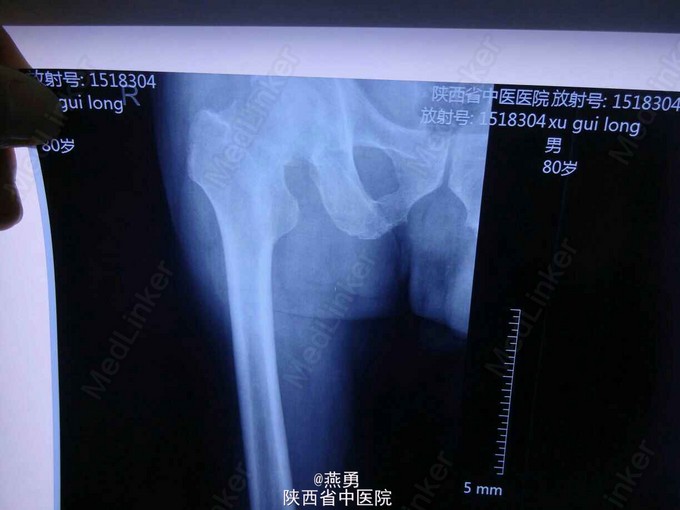

81岁男性患者,一个月前不慎摔倒右髋部着地,当即右髋部疼痛,活动困难,被动活动疼痛明显加重,近来患者自觉疼痛无缓解,活动受限,遂到我院就诊。 患者五年前曾在其他医院行结肠癌根治术 。

右下肢外展外旋畸形,较健侧短缩1CM,右髋关节肿胀不明显,压痛(+), 右腹股沟中点压痛(+),右下肢纵轴叩击痛(+)。

诊断:右股骨颈骨折,骨囊肿待查。治疗:右侧人工股骨头置换术,病灶清除探查术。麻醉生效后,常规逐层切开及暴露可见股骨颈颈中型骨折,清除周围纤维增生挛缩及瘢痕组织,取头器取出断裂的股骨头,患肢内收外旋脱位后,截骨,髓腔开口及扩髓,探针可见小转子内测约0.5*0.8cm病灶空腔,内壁完整,刮除腔内病灶送病检,填入少量抗生素型骨水泥,装入生物型股骨柄,置入双动头股骨头假体,复位,见右侧髋关节屈伸旋转活动良好,未出现脱位,双下肢等长。冲洗,清点纱布器械后,放置引流,关闭伤口加压包扎。 术后安返病房行预防感染预防血栓及对症治疗。